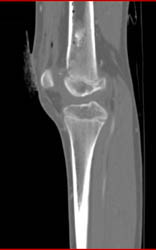

Gout